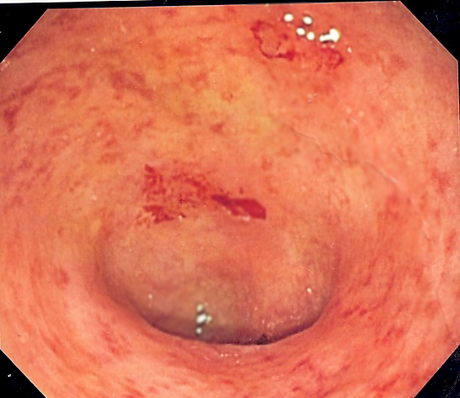

-Usted tiene colitis ulcerosa, 40 centímetros de la parte baja del colon con úlceras. Es una enfermedad crónica e incurable, lo acompañará toda su vida.

Investigando veo que la colitis es esto: